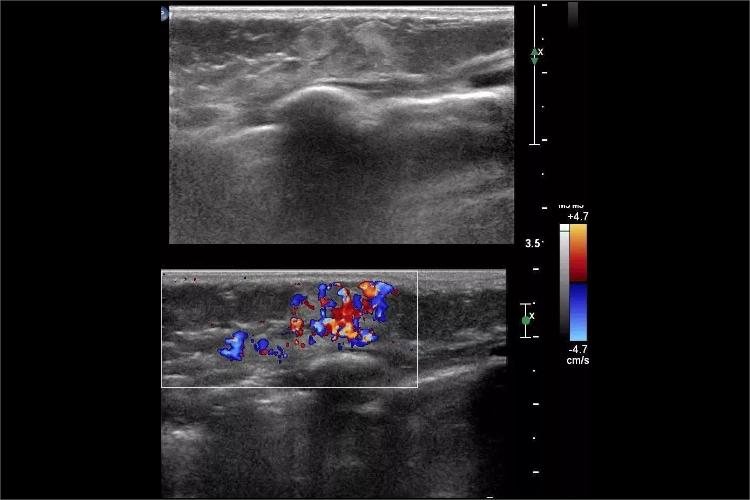

血管脂肪瘤:富含毛细血管型小血管的脂肪瘤,外形呈圆形、椭圆形,内部高回声为主,高低回声相间,境界欠清晰,包膜回声不明显。